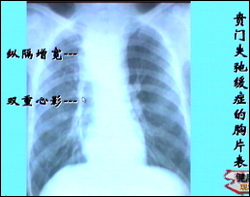

主持人:有哪些检查呢? 王伟:通常对于吞咽困难的患者都会做以下几种检查包括照X光片、食管钡餐造影、食管测压检查等,根据病人的不同情况采取不同的检查。来看一张图,贲门失弛缓症患者通常表现为上纵隔增宽,还会出现双重心影,这是因为食管扩张以后产生了一个比较宽大的食管,在胸片上就表现为纵隔增宽和双重心影。食管钡餐检查是一个最常用的检查,这个检查是诊断贲门失弛缓症的一个关键的检查,它的准确性和敏感性都比较高,食管吞钡检查是将一杯比较稀的造影剂吞入食管,通过照相可以显示出食管的形状以及运动的情况,贲门失弛缓症在钡餐检查的过程中可能会出现一些典型的表现,如图第一张图显示食管近端高度扩张,下端狭窄,这个狭窄段一般有3-5公分长,但是管壁比较柔软而且规则,这是与食管癌不一样的,我们称之为鸟嘴状改变。中间这张图的图形比较像萝卜根须的形状,因此称为萝卜根状。最后一张图也是由于食道根部的狭窄,吞咽的钡剂完全不能下咽,淤积的钡剂像一个漏斗一样,因此称为漏斗状。有了这些典型的表现,通常在临床上就可以诊断为贲门失弛缓症。